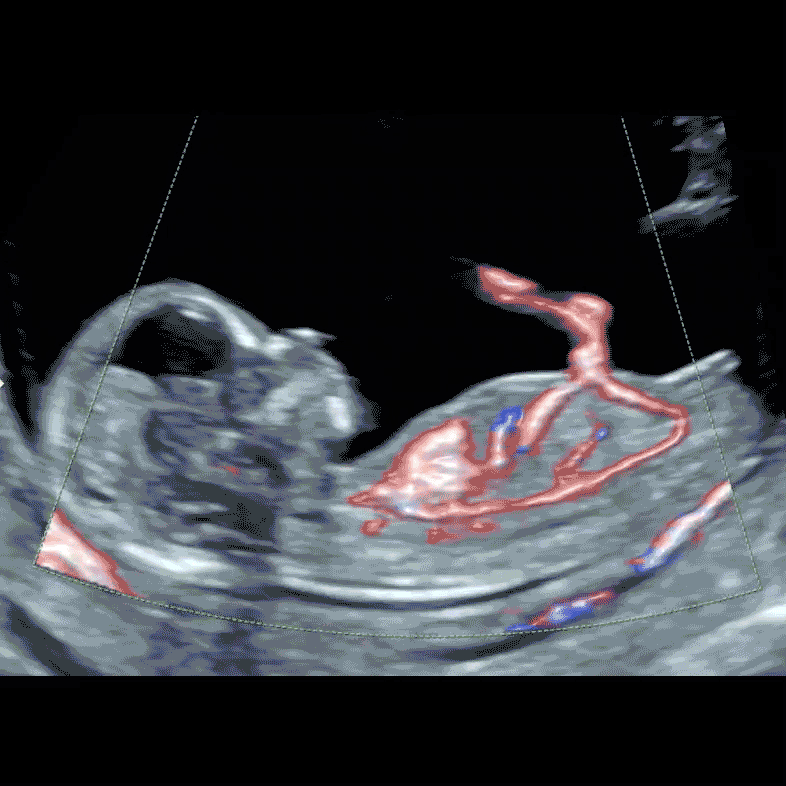

Early diagnosis of increased NT triggers the SMART NT protocol. Detection of lethal anomalies, such as acrania or body stalk anomaly, serves as an exclusion criterion for NIPT.

A specialist scan aimed at excluding structural anomalies associated with high NT, particularly heart defects. It also assesses changes in NT over time, which provide important prognostic information.